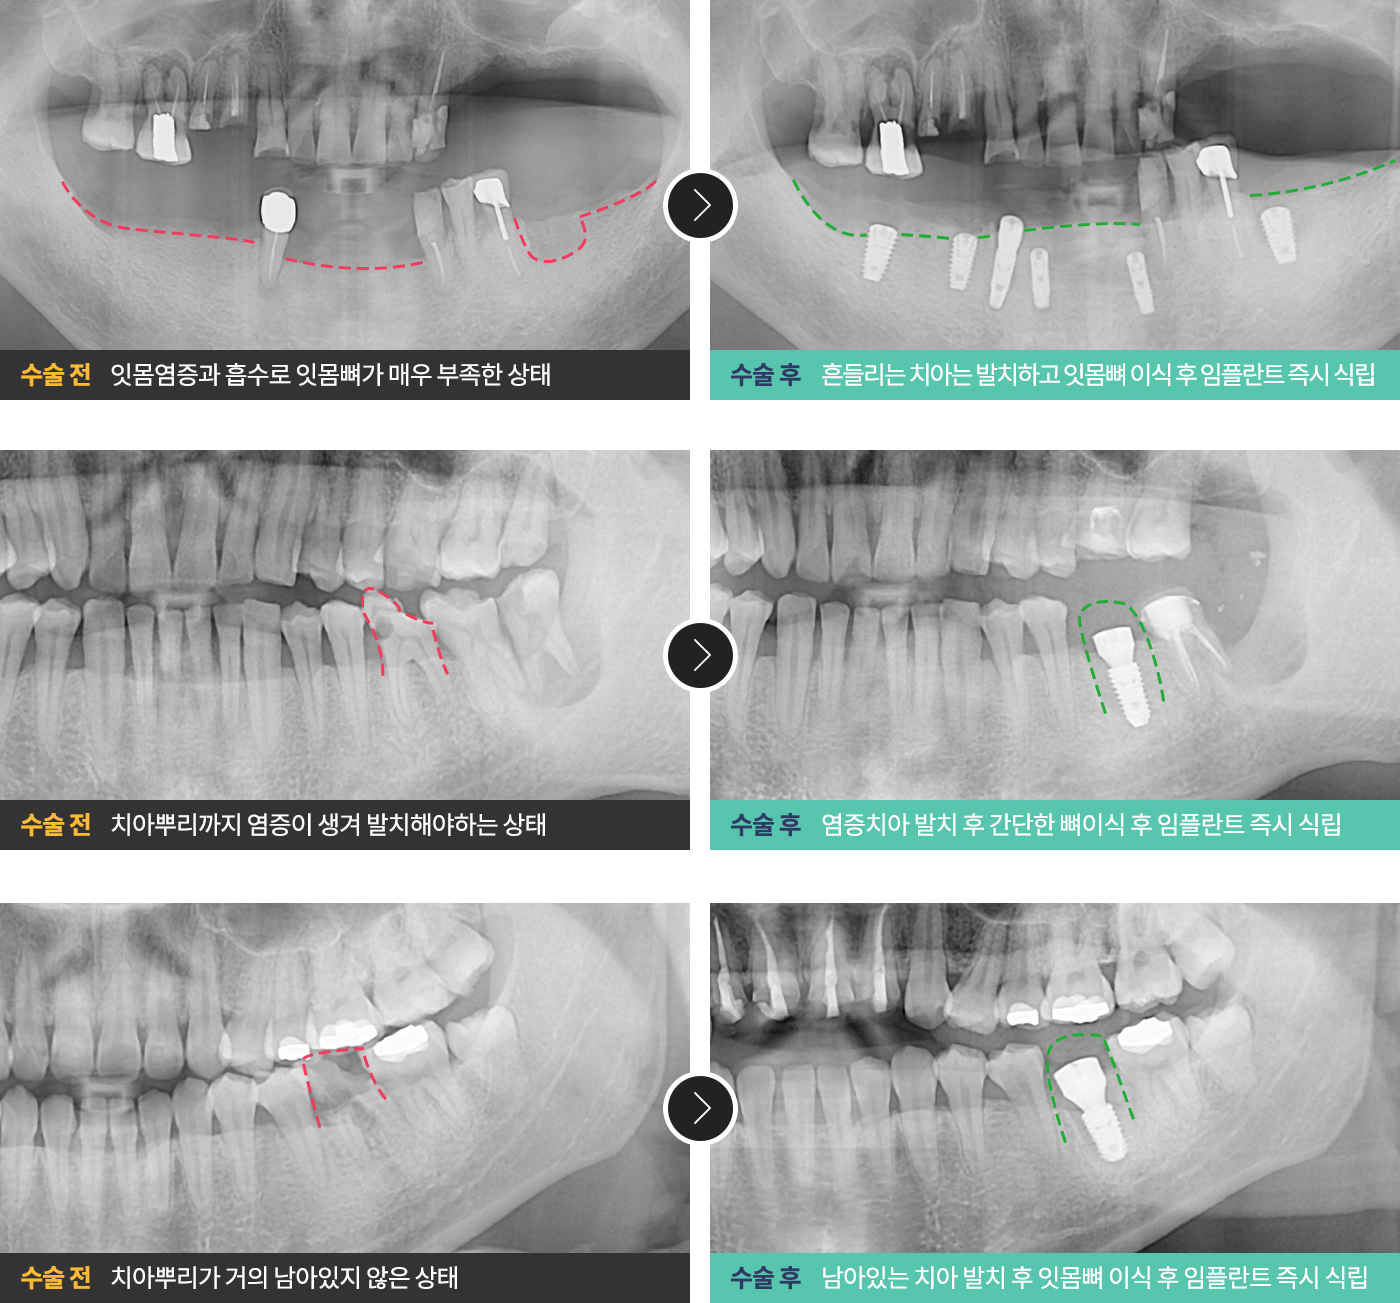

발치해야하는치아를 뽑은 직후 필요시 잇몸뼈까지 이식 후 임플란트를 식립하는 방법입니다.

발치를 한 즉시 임플란트 픽스쳐를 식립하기 때문에

발치 후 회복을 거쳐야하는 기존의 임플란트 방식보다 빠르고 안정적입니다.

치료 사례